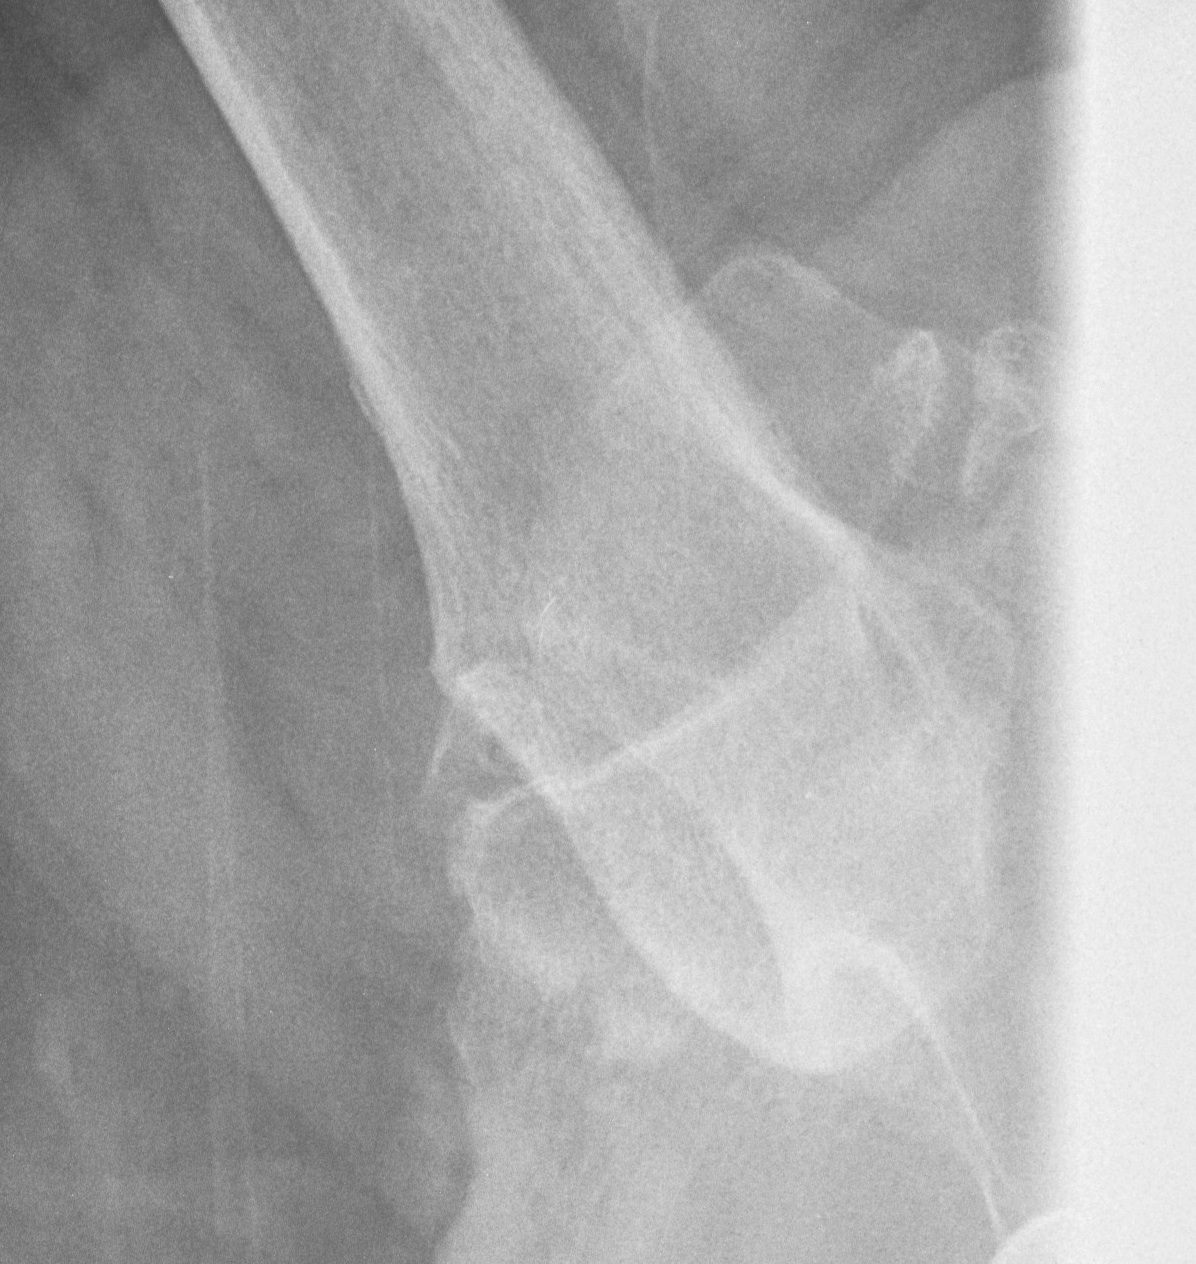

Xray

Signs of chronic shoulder dislocation